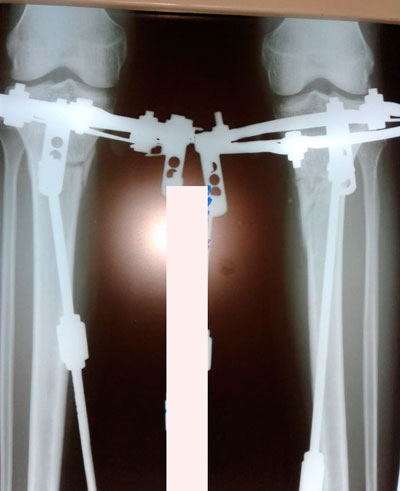

перед крутками

IMG_3185-14-05-19-11-58.JPG